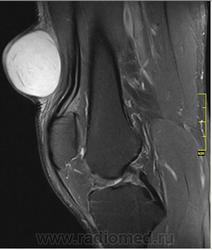

При осмотре атерома представляет собой опухолевидное образование округлой формы, мягкой консистенции размером от 5 до 40 мм и более. Кожа над атеромой обычно не изменена, однако в случае присоединения воспаления может иметь красноватый оттенок. Атерома подвижна вместе с окружающими тканями, безболезненна. Атерома может оставаться маленькой на протяжении многих лет, либо увеличиваться.

Иногда атерома сообщается с поверхностью кожи через небольшое отверстие, через которое могут отделяться атероматозные массы. Часто атеромы нагнаиваются, кроме этого, может происходить разрыв атеромы в подкожную клетчатку.